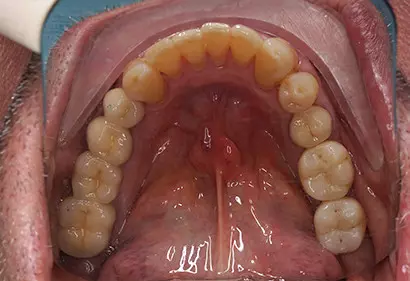

- Протезирование

- Коронки